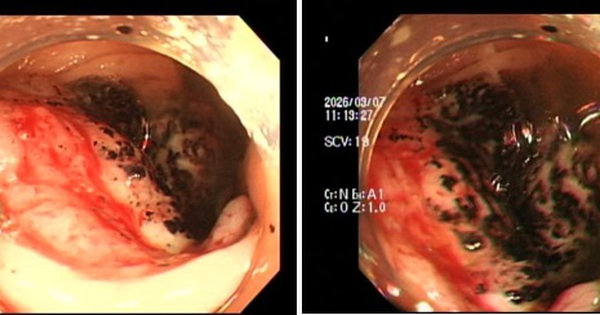

Mệt mỏi, uể oải, da xanh, rất nhiều người bị ung thư đại trực tràng thuộc thế hệ 9X đến khám với dấu hiệu này, được Bệnh viện Nhân dân 115 cảnh báo.